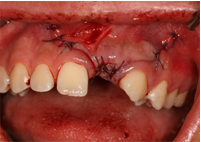

![]() |

| Cấy ghép implant R24 |

LẤY XƯƠNG CẰM GHÉP VÀO VỊ TRÍ KHUYẾT HỔNG

Vị trí khuyết hổng xương ổ răng

Thiếu xương khi ghép implant

Phẫu thuật lấy xương cằm

Ghép xương cằm và xương hạt

Dùng màng tự tiêu

Khâu đóng kín vết thương

Lành thương sau 10 ngày